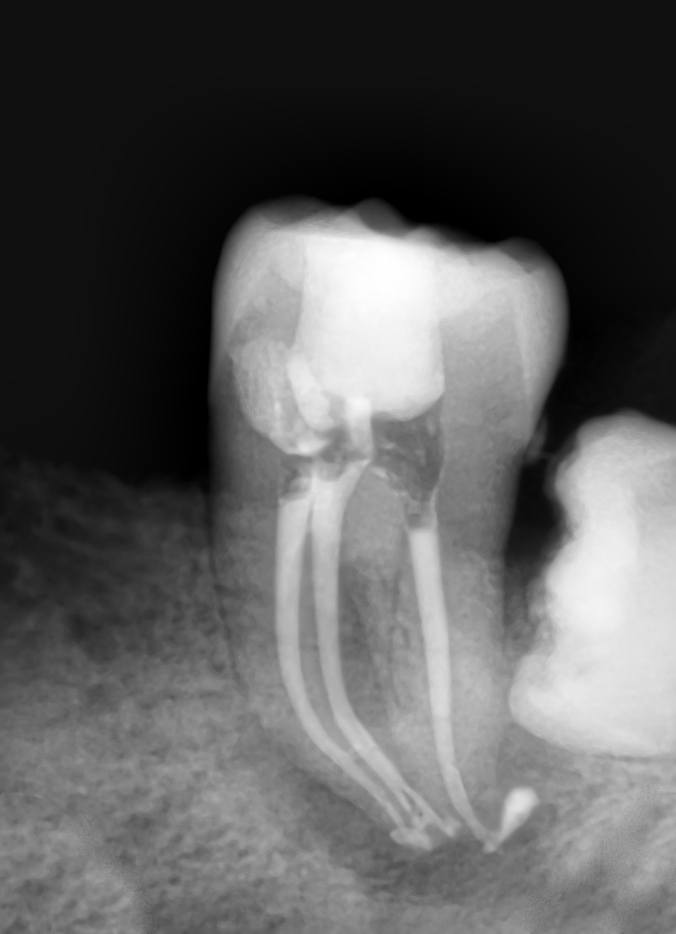

Pacienții necesită un tratament endodontic atunci când la nivelul camerei pulpare sau a canalului radicular există inflamație sau infecție, din cauza unei carii profunde, a unei fisuri sau provocată de un traumatism accidental. Poate fi realizat într-o singură ședință sau în mai multe, în funcție de complexitatea cazului.

În timpul tratamentului, medicul endodont curăță, dezinfectează, prepară canalele radiculare și obturează etanș spațiul creat. Dinții cu destrucții coronare masive necesită ranforsare cu pivoți de fibră de sticlă, iar ulterior vor fi șlefuiți și acoperiți cu lucrări protetice ce redau rezistența structurii dentare restante.